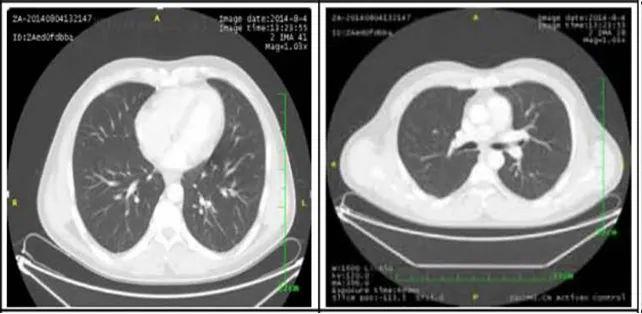

2. 肺部病灶治疗前后核磁对比:

肺部转移病灶在用药后2个月明显缩小,4个月后病灶基本消失。

治疗前

治疗2个月

治疗4个月

治疗6个月

治疗16个月